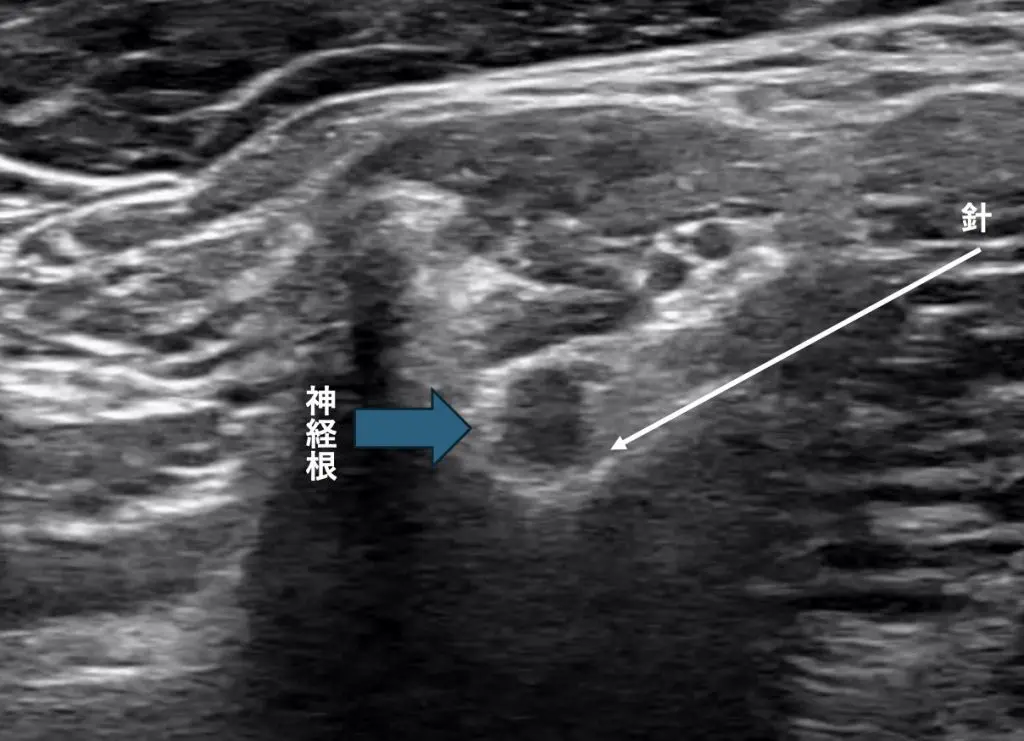

従来のエコーでの神経根ブロックは以前私もこちらのブログでご紹介した通り、神経根を骨の形を目印として見つけて神経の周りに注射をします。ただそれだと中枢部まで届いていない可能性があるのです。

従来はこのように神経の同定をして神経ブロックをしていました。

朴法はこのレベルから少し頭側にエコープローブを移動します。そうすることで後結節という骨が消えて前面に椎骨動脈、後面(背側)に神経根というビューとなります。

ではこれをエコーでしてみるとどうなるかということですが、なかなか難易度が高い

脊髄に入っていく神経根とその隣にある椎骨動脈を確認します。

ただ、針を持っていくのは少し熟練が必要です。